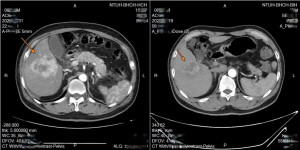

• 低血糖反覆發作竟非糖尿病 男子多次昏迷送醫揪出25公分罕見肺腫瘤 (23:34)

養生男不菸不酒 左頸微凸竟藏12公分巨瘤

現代人注重養生,但生活規律、遠離菸酒就一定能與癌症絕緣嗎?台中一名年約60歲的企業主,平日生活極其自律,不僅菸酒不沾,更維持早睡早起、規律運動的良好習慣,是親友眼中標準的「健康模範生」。不料,今年初他在晨間盥洗照鏡...